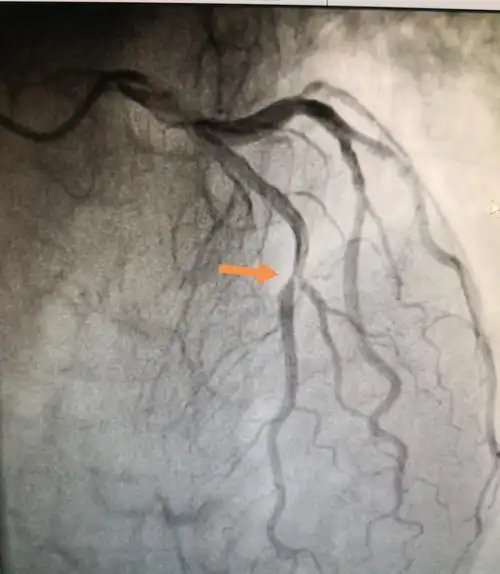

先天性心脏病微创不开刀介入封堵手术,经胸封堵术,小切口或常规切口

查"缺"补漏,让心更完美-先心病治疗应尽早

挽救先心病龙凤胎兄妹我院心血管内科和普外一科联合完成mdt手术